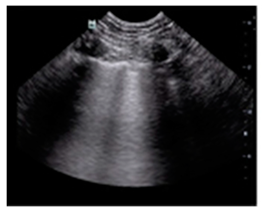

| Pneumonia/pulmonary consolidation | “Lung consolidation occurs due to a significant loss of aeration. It appears as a tissue-like echotexture, with a superficial boundary at the pleural line and a deep, irregular boundary with the aerated lung, known as the ’shred sign.’” | ![]() |